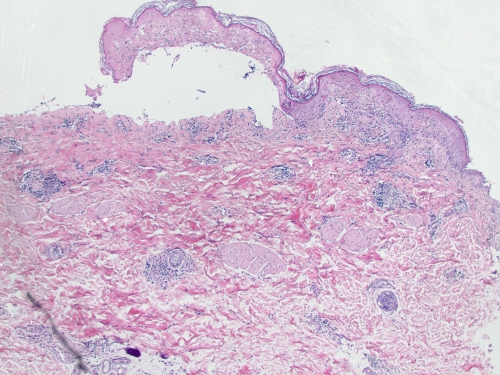

Разновидностью чего является центробежная эритема биетта - фото презентация